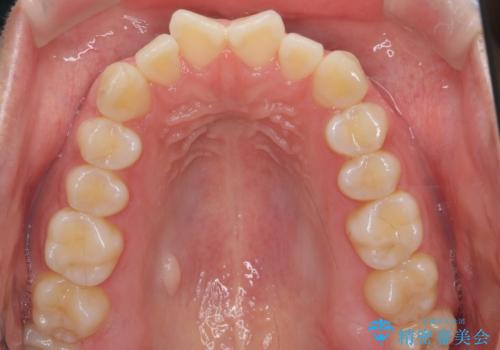

インビザライン モニター治療 前歯のねじれをまっすぐに

- 前歯のねじれを主訴に来院。

インビザラインの部分矯正コースではなく全体矯正コースをご希望でした。

前歯のねじれやがたつきだったため、モニター治療での低価格でのご提案が可能でした。

年齢が10代なこともあり、歯の動きは非常によく、リファインメントなしできれいに並びました。

下の前歯を少し削合して並べています。